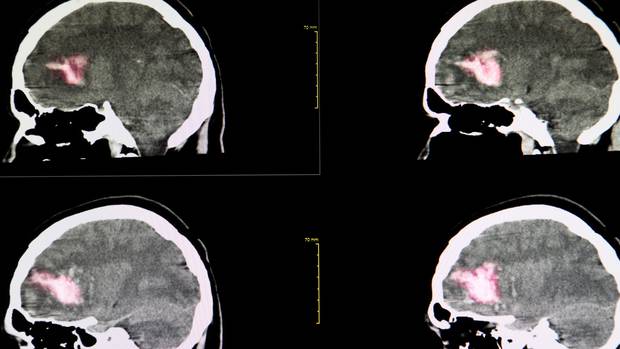

Bunyavirus là tên gọi chung của một nhóm virus gây bệnh màng não vô khuẩn. Đặc biệt nhóm virus này gây viêm não California và viêm não Crosse gây hôn mê, tỉ lệ liệt và tử vong cao. Loại virus này được lây truyền chủ yếu do các loài gặm nhấm, động vật chân đốt, động vật có xương sống... chủ yếu là bọ ve, ve chó và muỗi.

Khi nhiễm virus Bunya, cơ thể người bệnh sẽ ảnh hưởng thế nào?

Trung tâm Kiểm soát Dịch bệnh Đài Loan cho biết loại bunyavirus mới này có tỷ lệ tử vong khoảng 10%. Các triệu chứng ban đầu khi nhiễm virus Bunya là sốt, buồn nôn, ói, rối loạn tri giác đưa đến hôn mê, co giật. Ở thể nhẹ, một số triệu chứng của người bệnh có thể tự khỏi, tuy nhiên ở thể nặng, bệnh nhân có thể bị rối loạn chức năng đa cơ quan, suy đa tạng, thậm chí là tử vong. Đối tượng dễ mắc bệnh và tử vong nhất là người già.